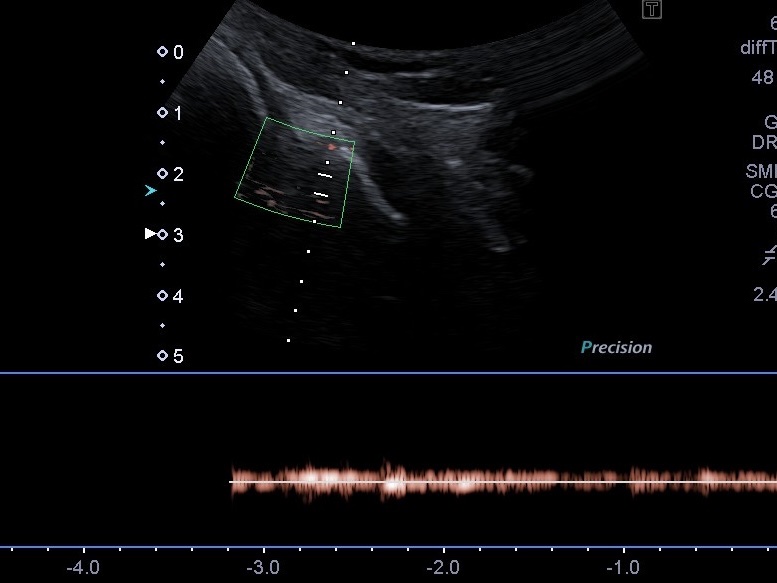

- Еластографія зсувної хвилі: Дозволяє прослідкувати процес фіброзування розриву та зміну жорсткості меніска під час лікування. Це дає розуміння, наскільки успішно проходить відновлення тканин.

- Технологія SMI (візуалізація мікроциркуляторного русла): Це унікальний режим, що дозволяє побачити найдрібніші судини. Завдяки SMI ми можемо визначити кровопостачання «червоної зони» меніска та зафіксувати рідкісне явище — неоангіогенез (появу нових судин) у «білій зоні» після травми.

Розриви в червоній зоні (де є кровопостачання) загоюються набагато швидше. Біла зона позбавлена судин, тому відновлення там проходить важче. На звичайному УЗД (В-режимі) відрізнити ці зони неможливо, але режим SMI дозволяє відмежувати їх завдяки доплерівському сигналу від мікросудин.